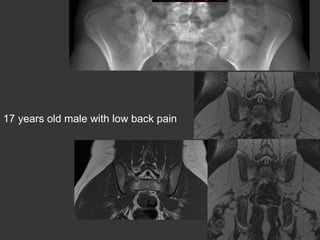

17 years old male with low back pain

Inflam. Rh.